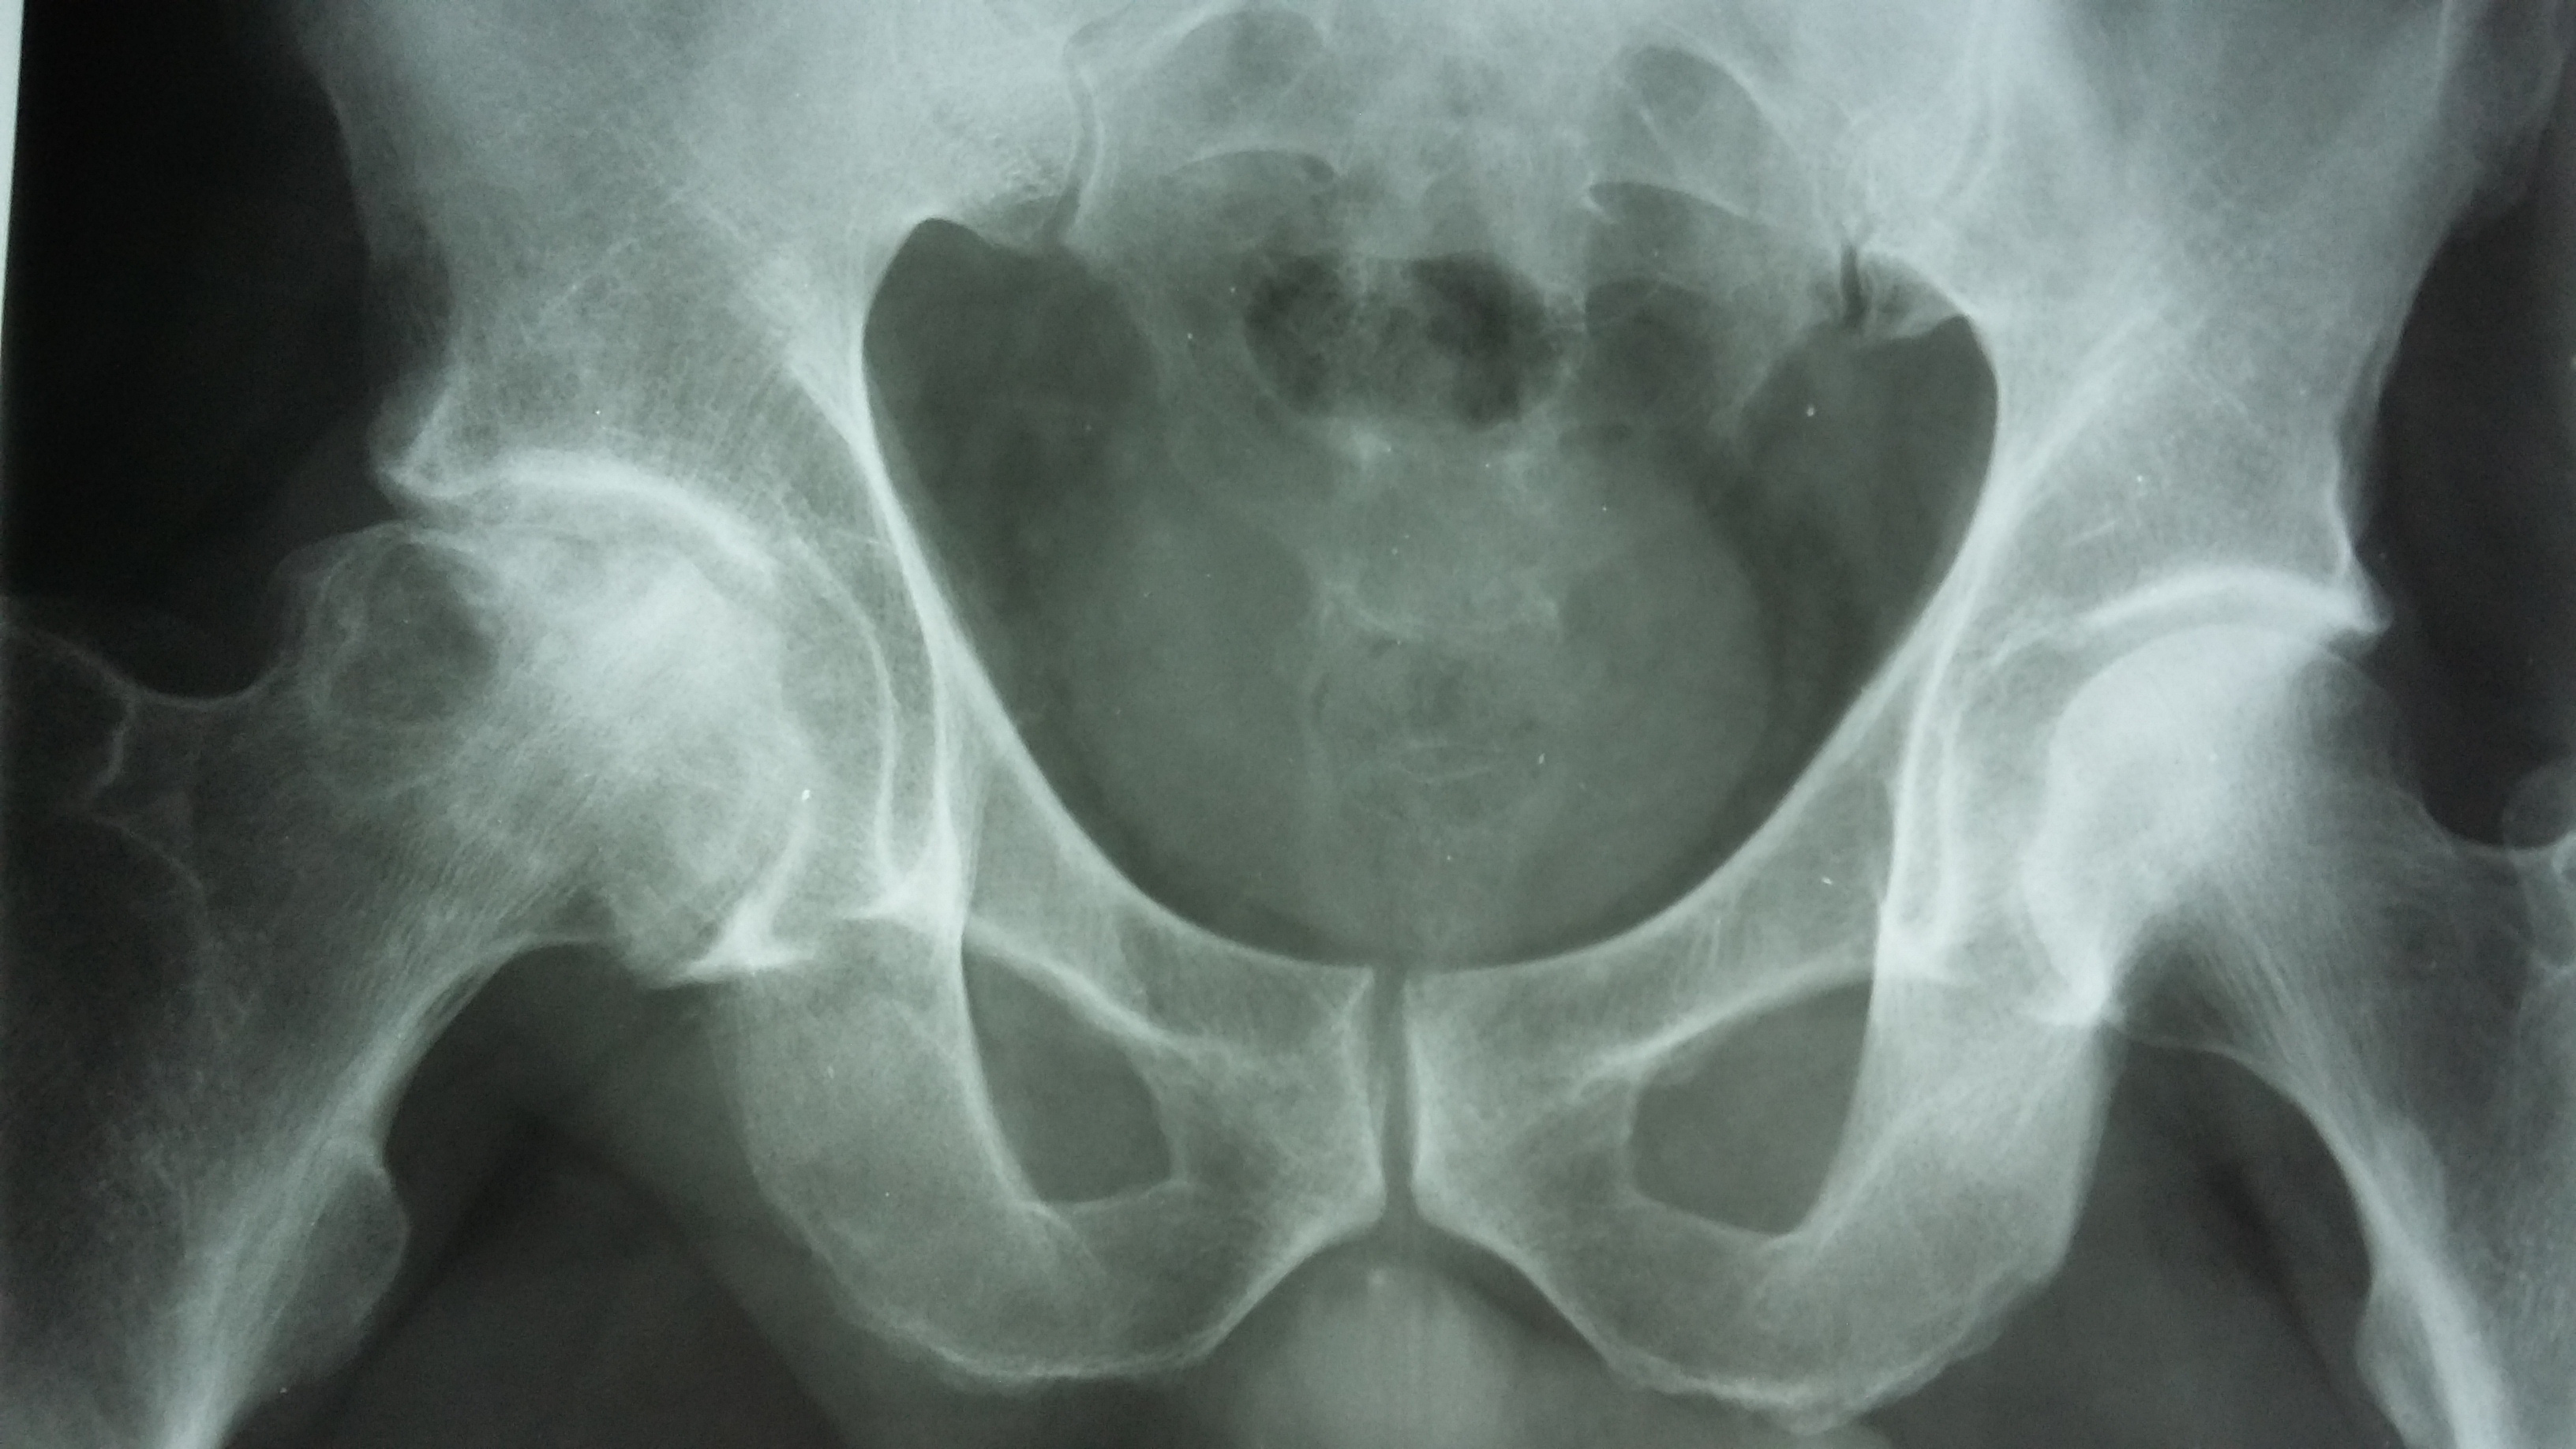

Некроз тазобедренного сустава: Фотографии и особенности лечения